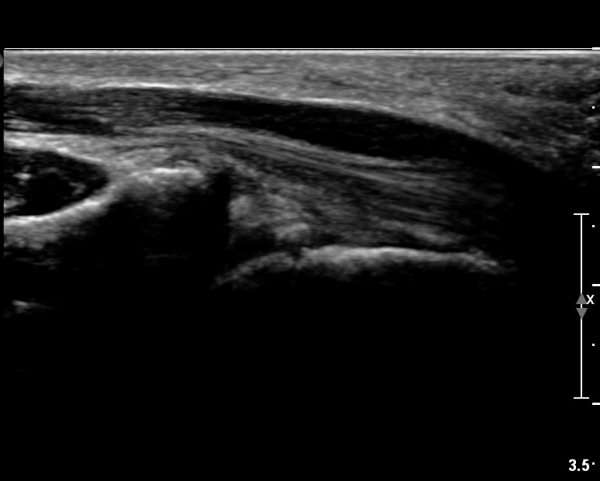

ÀÌ·± ¸ð½ÀÀº ¼Õ¸ñÀÇ ¿ù»ó°ñ ºÎÀ§(»çÁø 3, 4)¸¦ Áö³ª ¼ö±Ù°ü ±ÙÀ§ºÎ ±îÁö À̾îÁü(»çÁø 5).

ÇÏŰ½ºÆ½(°íÁÖÆÄ) ŽÃËÀÚ¸¦·Î °üÂûµÈ ¸ð½À¿¡¼­ Á¤Áß½Å°æ ºÎºÐ ½Å°æ´Ù¹ßÀÇ Àú¿¡ÄÚ

º¯È­°¡ ¶Ñ·ÈÇÔ(»çÁø 6, 7).